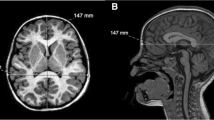

This is a report of new case of PIBI(D)S, a rare autosomal recessive syndrome characterized by photosensitivity, ichthyosis, brittle sulfur-deficient hair (trichothiodystrophy), impaired intelligence, decreased fertility, and short stature. Bilateral cataract and axial osteosclerosis were also detected. Magnetic resonance imaging (MRI) revealed diffuse central nervous system dysmyelination, a finding also described in the only three other reported cases in which MRI was performed. The paper also considers certain similarities in neurological signs and neuroradiological findings between PIBI(D)S, Cockayne syndrome, and xeroderma pigmentosum β all of which are inherited diseases characterized by photosensitivity and DNA repair defect.

Peserico A, Battistella PA, Bertoli P (1992) MRI of a very rare hereditary ectodermal dysplasia: PIBI(D)S. Neuroradiology 34:316β317